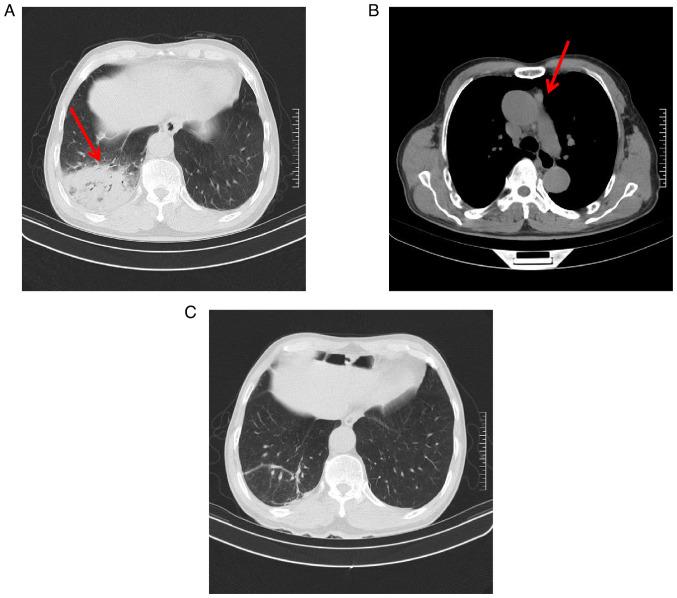

The case of a patient with type B3 thymomacomorbid with pneumonia exhibiting rare features is presented in the current report. The patient was admitted at the Second Affiliated Hospital of Jiaxing University (Jiaxing, China) with a history of direct contact with poultry. Clinical manifestations included fever, shivers, cough, fatigue and poor appetite. Chest computed tomography (CT) indicated right lung pneumonia, while metagenomics next-generation sequencing using bronchoalveolar lavage fluid confirmed infection with . Additionally, positron emission tomography-CT suggested the presence of thymoma. After surgery and treatment with doxycycline and imipenem cilastatin, the patient was discharged showing signs of improvement.

本报告介绍了一例合并肺炎的B3型胸腺瘤患者的病例,该病例具有罕见特征。患者因有与家禽直接接触史,入住嘉兴学院附属第二医院(中国嘉兴)。临床表现包括发热、寒战、咳嗽、乏力和食欲减退。胸部计算机断层扫描(CT)显示右肺肺炎,而使用支气管肺泡灌洗液进行的宏基因组学下一代测序证实感染了……此外,正电子发射断层扫描-CT提示存在胸腺瘤。经过手术以及强力霉素和亚胺培南西司他丁治疗后,患者出院,病情有所改善。